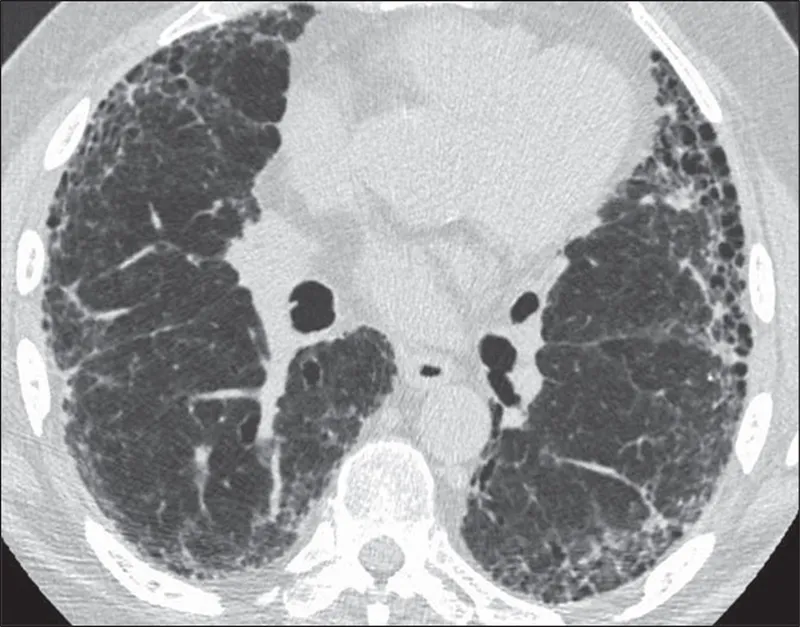

- HRCT Chest (essential for diagnosis):

- Bilateral, basal, subpleural reticulation.

- Honeycomb cysts.

- Traction bronchiectasis.

- Absence of: extensive Ground Glass Opacities (GGO), nodules, consolidation.

- ⭐ > The UIP pattern on HRCT, characterized by subpleural, basal predominant honeycombing, is crucial for IPF diagnosis.

- IPF: UIP pattern (honeycombing, traction bronchiectasis) on HRCT; treat with Pirfenidone/Nintedanib.